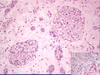

Acute TID; characterized by active inflammation; see eosinophils and lymphocytes (left) and neutrophils (right)

Acute TID; active inflammatory cells in interstitium: lymphocytes, neutrophils, plasma cells, macrophages

Acute interstitial nephritis; infiltration of plasma cells, eosinophils, lymphyocytes, macrophages; also see edema

Acute interstitial nephritis; diffuse infiltration of inflammatory cells; tubules relatively unaffected.